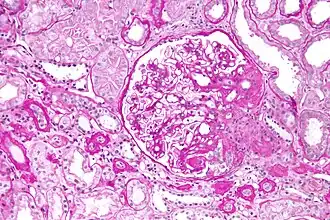

Световая микроскопия нефробиоптата, PAS-реакция. Фокально-сегментарный гломерулосклероз, перихиллярный вариант.

При гистологическом исследовании отмечается склерозирование лишь части клубочков, к тому же повреждённые клубочки склерозированы не полностью, а сегментарно, что позволяет провести дифференциальную диагностику с другими клубочковыми заболеваниями почек.

2. Перихиллярный — склерозирование зоны сосудов